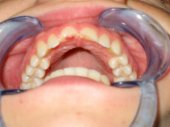

Una mordida cruzada anterior es el inicio visual

de una progenie mandibular. Sólo si se frena y corrige a una edad

temprana, que es cuando se originan, recupera de manera efectiva el desarrollo

normal.